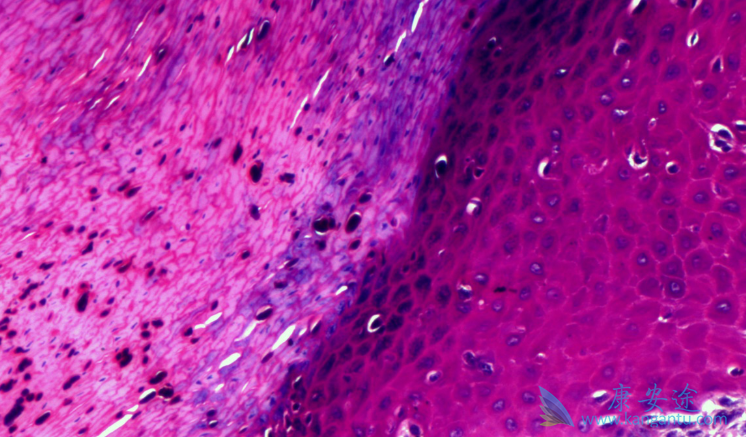

什么是恶性黑色素瘤?恶性黑色素瘤是皮肤癌,是恶性程度高、发病率增长迅速的肿瘤之一。患者往往不能及时发现症状,等到就诊时,多数已经晚期。我国此种病的发病率逐年增长,估计每年新发病例约2万例。此种瘤大多发生于肢端脚底、手掌等部位,而容易受到摩擦的部位更可能发生恶变。如果发现有“疑似”情况,可以到医院门诊进行手术。

如何进行鉴别黑色素瘤?鉴别可应用“ABCDE”法则,分别代表了痣的五大异常特征。A(asymmetry)指痣的“对称性”:良性痣多为圆形或形状对称。B(borders)指“边缘”是否光滑整齐:边缘不整齐、模糊不清的要提高警惕。C(color)指“颜色”:不管是黑色、棕色还是蓝黑色,良性痣大多只有一个颜色,痣上出现杂色,就要注意了。D(diameter)是“直径”6mm:正常身体上的痣直径要小于6毫米,长在手掌、脚掌、手指、脚趾的痣,“标准”还要更小。E(elevation)局部凸起;上述ABCD不断增加扩大。